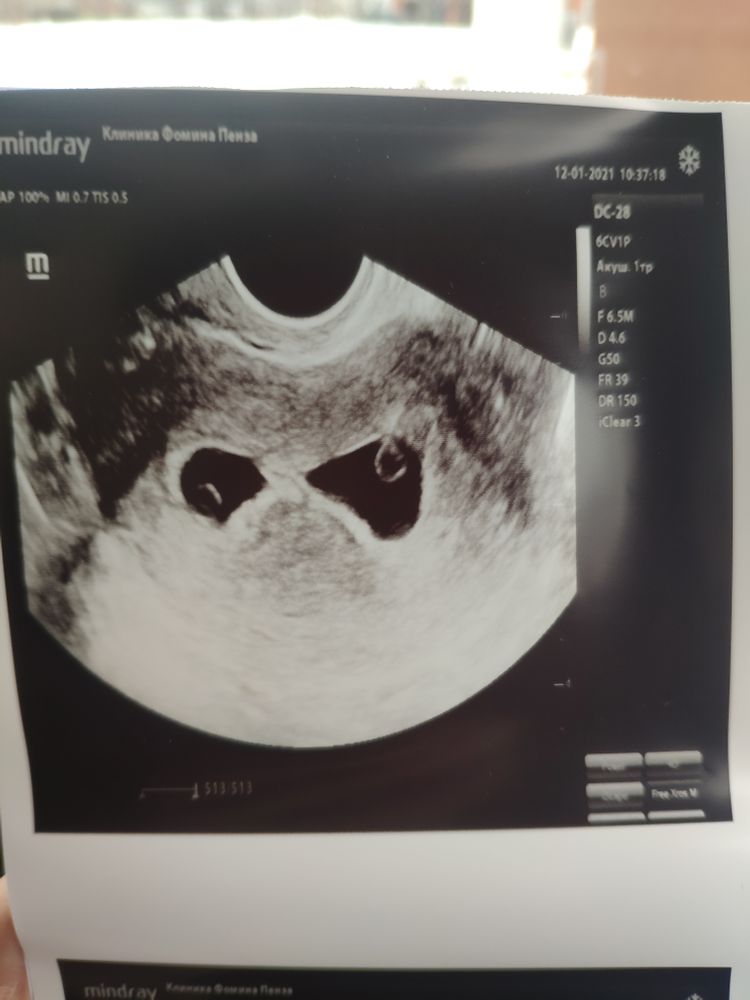

Первое УЗИ 25дпп

Я БЕРЕМЕННА !Вот и дождалась УЗИ, мазня продолжается.

Прижились оба))

Первый 4мм плодное яйцо 16, второй 3 мм плодное яйцо 14.

У обоих сердцебиение.